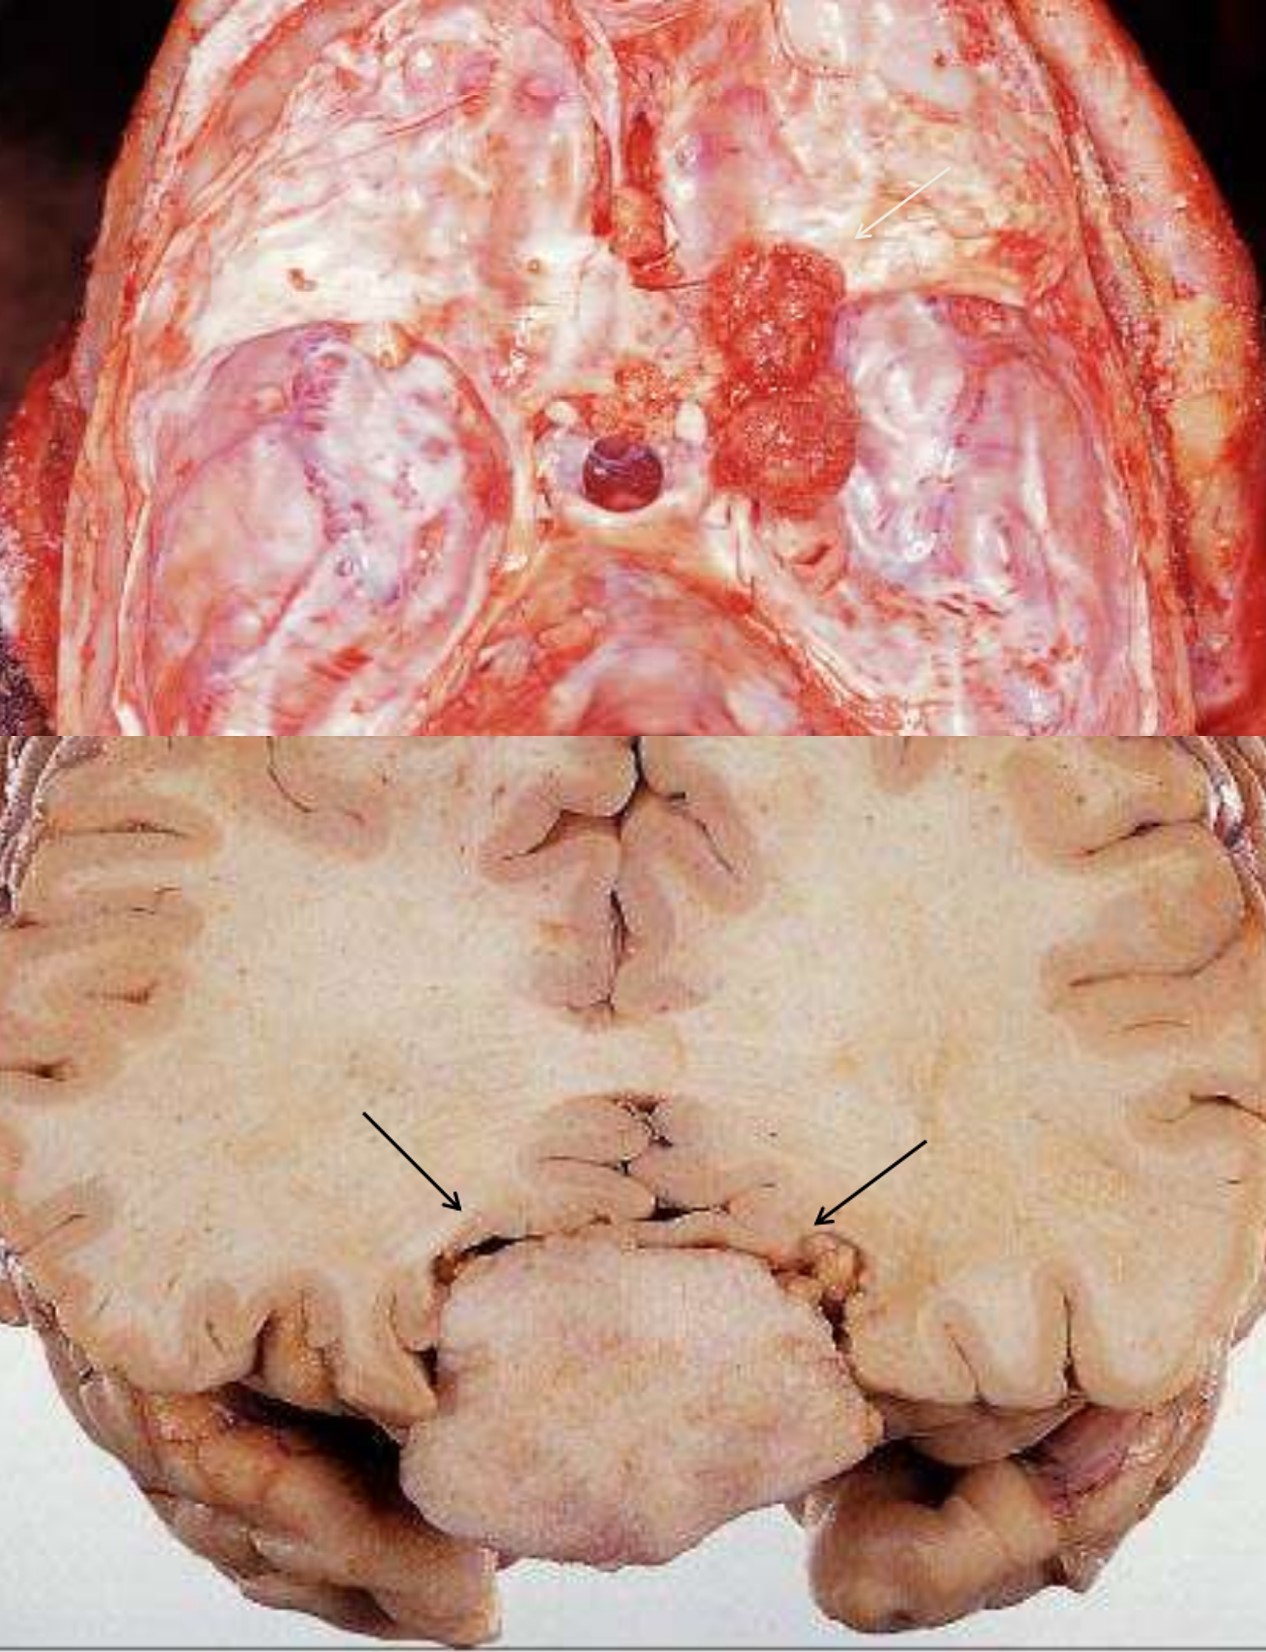

Medulloblastoma

- 20% of pediatric brain tumors

- Posterior fossa

- Spreads by CSF seeding along the subarachnoid space

Meningioma

- Benign tumors of adults

- Locations:

- Attached to dura, arise from arachnoid meningothelial cells